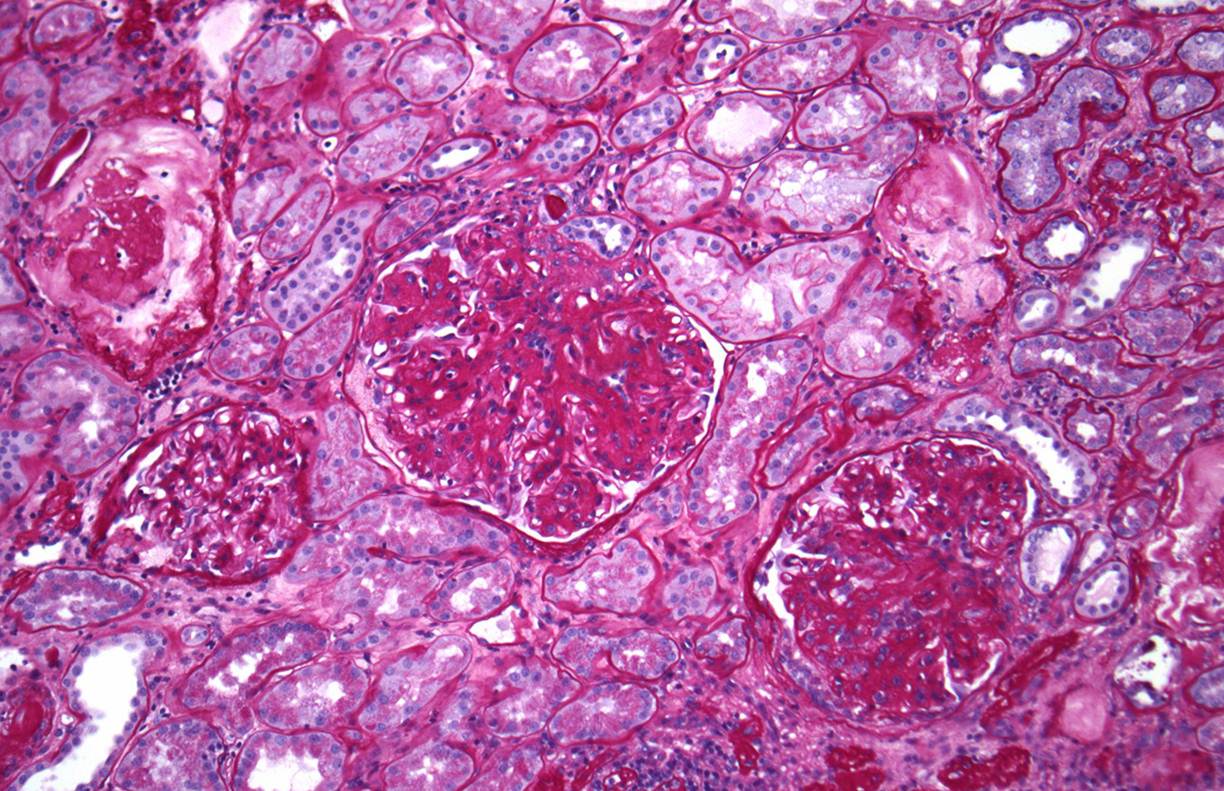

Higher power view of the preserved glomeruli revealed changes characteristic of diabetic nephropathy – nodular glomerulosclerosis.

Interestingly, he also had many tubules containing oxalate crystals, likely related to his previous gastric bypass surgery. There was associated acute tubular injury.